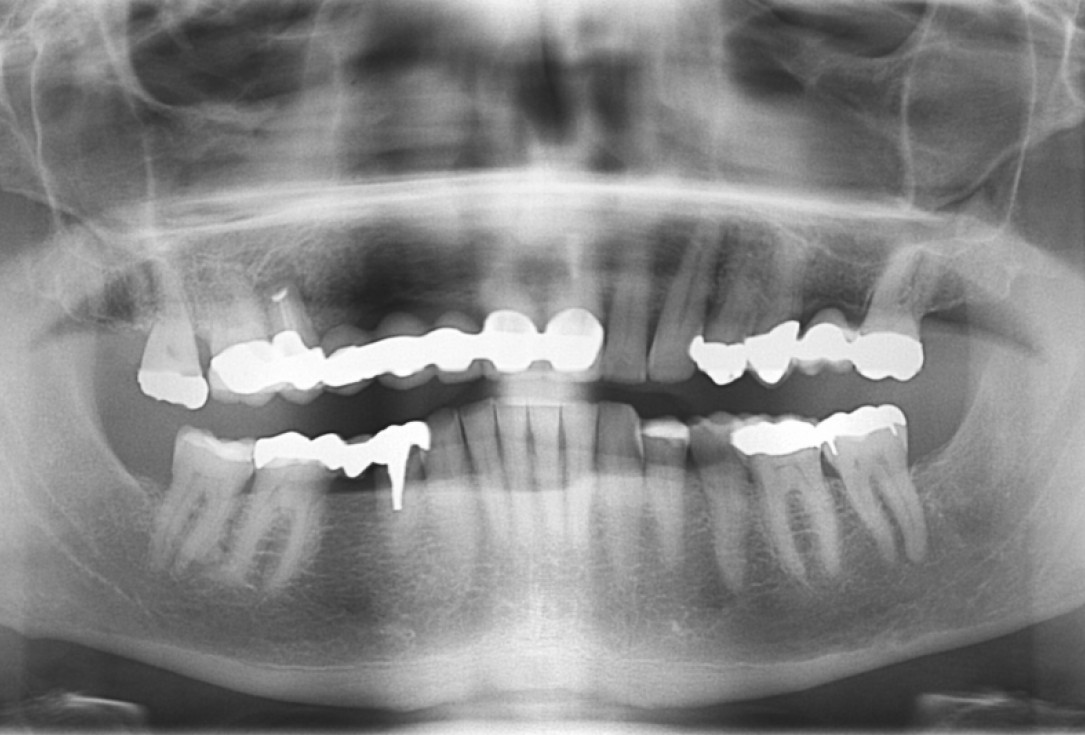

OPG of the initial situation – provision of missing denture in regio 44 to 47 by a resin-retained bridge